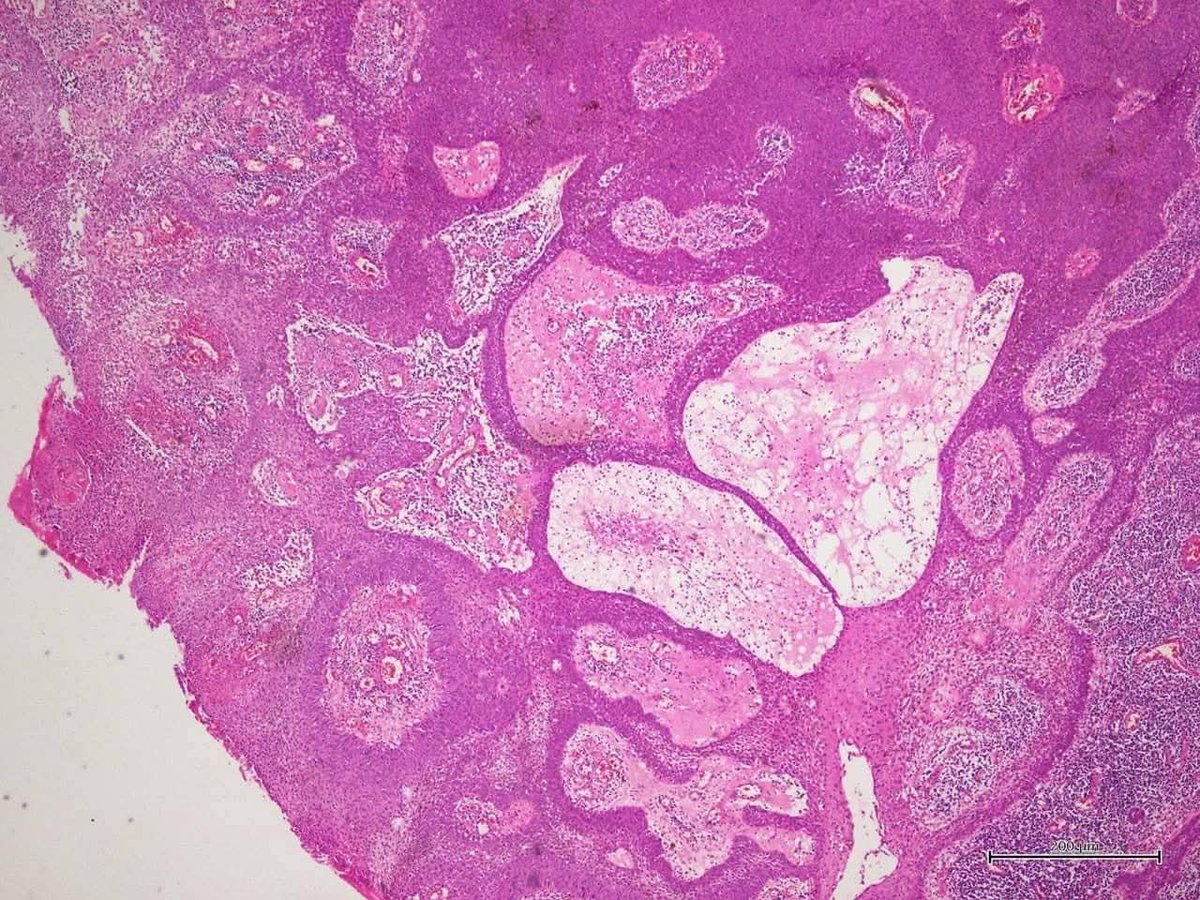

Regional lymph node metastasis of mucinous carcinoma, rectum with stage IIIC disease.

#pathology #GIPath #mucinous_carcinoma